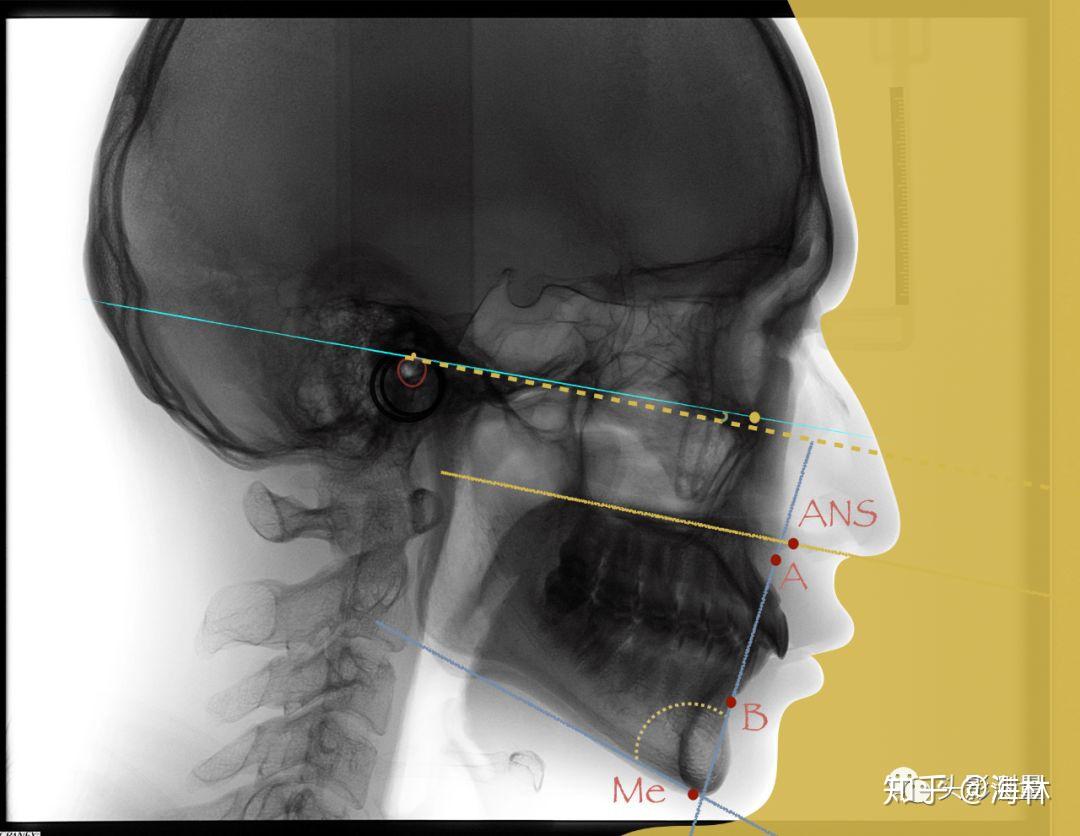

常用头影测量标记点及测量方法

正畸头影测量——常用标志点

描绘出一定的线角进行测量分析,从而了解牙颌,颅面软硬组织的结构特点